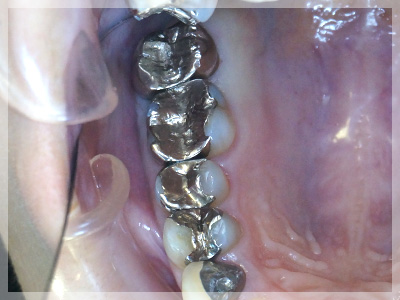

銀歯を除去し、イーマックスインレー3本、オールセラミッククラウン(色調調整無し)1本にて修復した症例

- 銀歯を白くしたいとのことでご来院されました。

- 右上4番5番6番をイーマックスインレー、7番をオールセラミッククラウン(色調調整無し)にて修復しました。